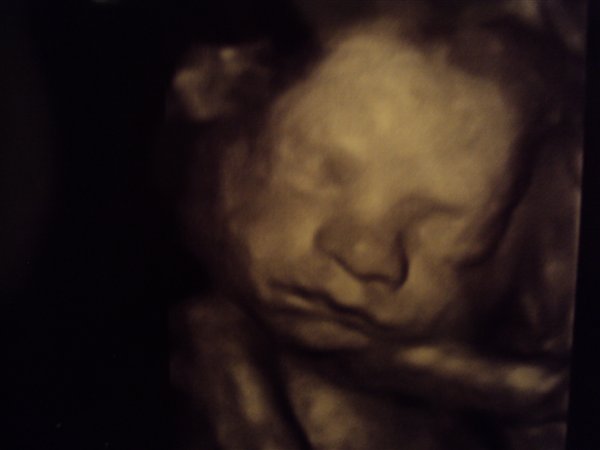

Vi fik afvide at han vejede 1 kg. her i uge 26 (25+4) Så han er en stor dreng. Han havde allerede fået deller og et tygt lag fedt på kroppen. Hun fortalte han formentlig ville være 4 kg. hvis han blev født til tiden, og ville bruge str. 56.

Sikke en dejlig dreng vi har der, og vi kan alle tydeligt se han har min mund. Hans tær er efter hans far - der var nemlig en af tærene der var lidt længer end de andre, hvilket min mand også har

Ellers kunne hun fortælle at næsen var meget lille og fin, og han allerede havde fået hår på hovedet.